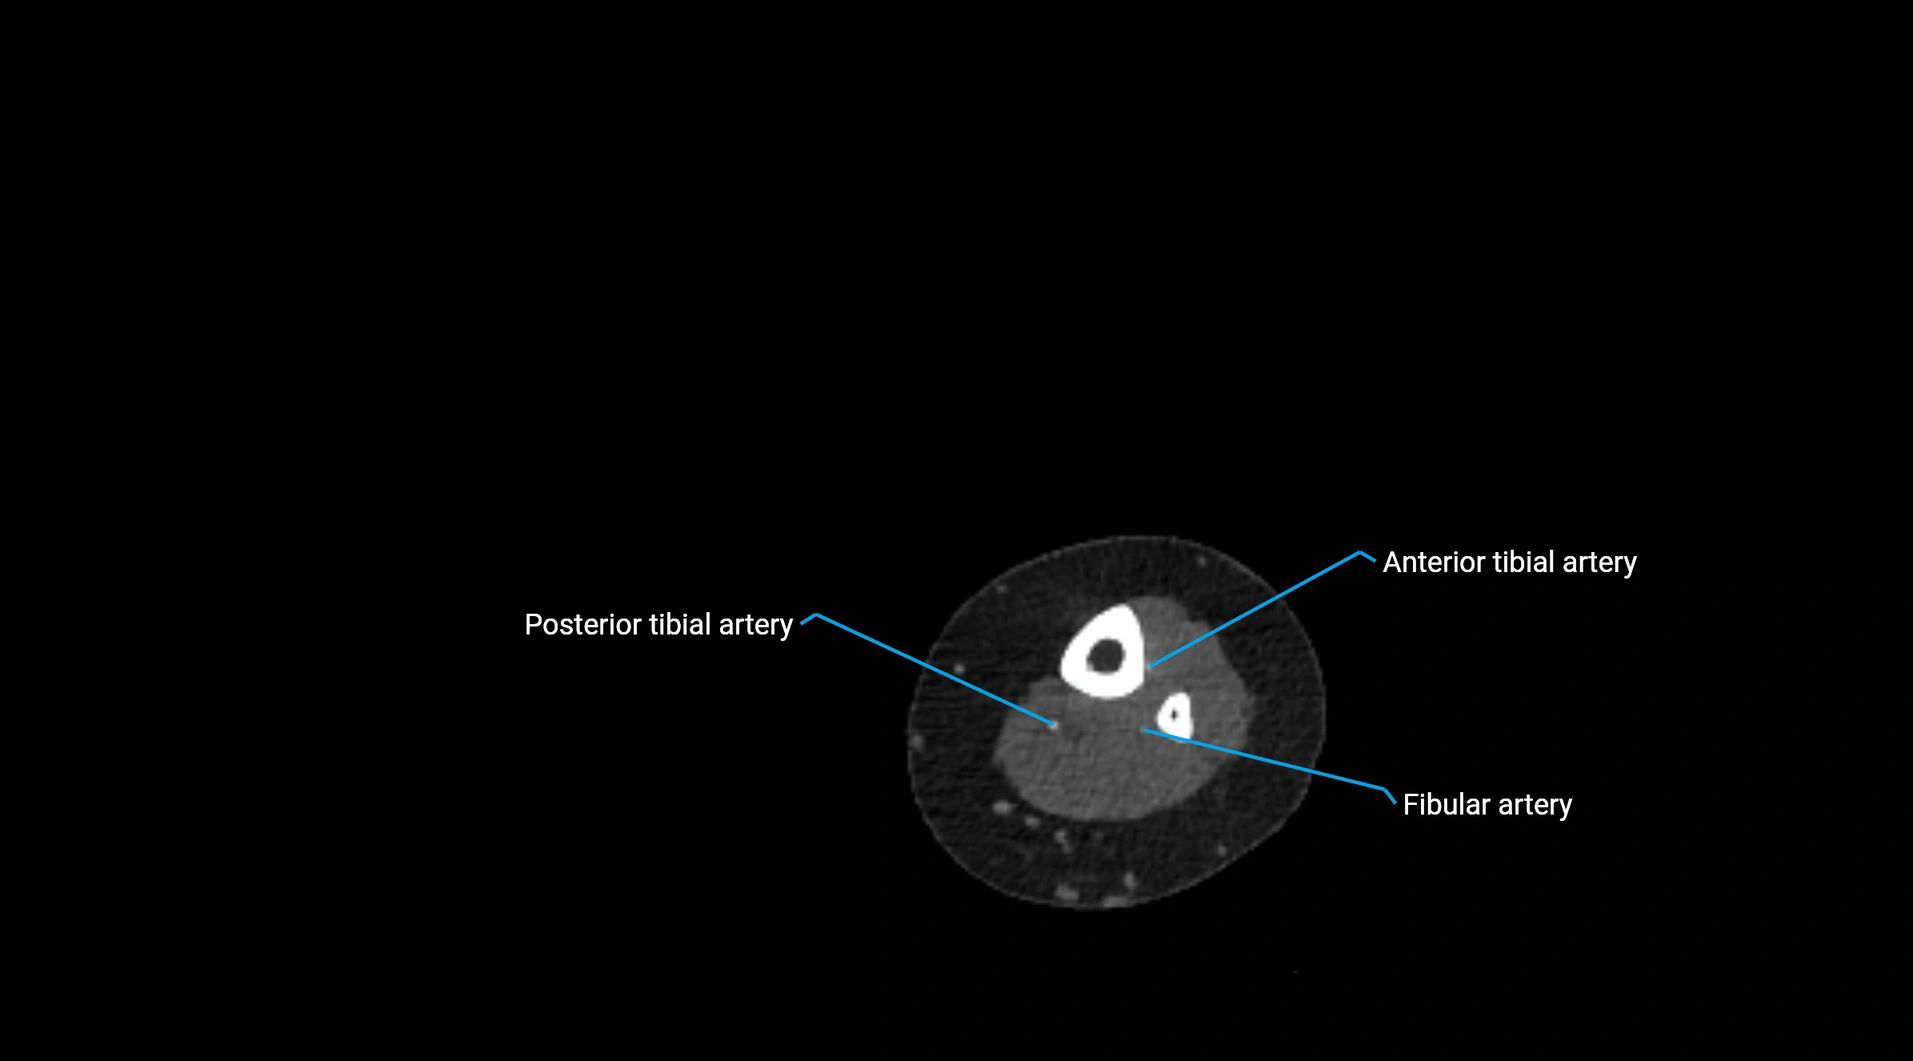

CT images

image